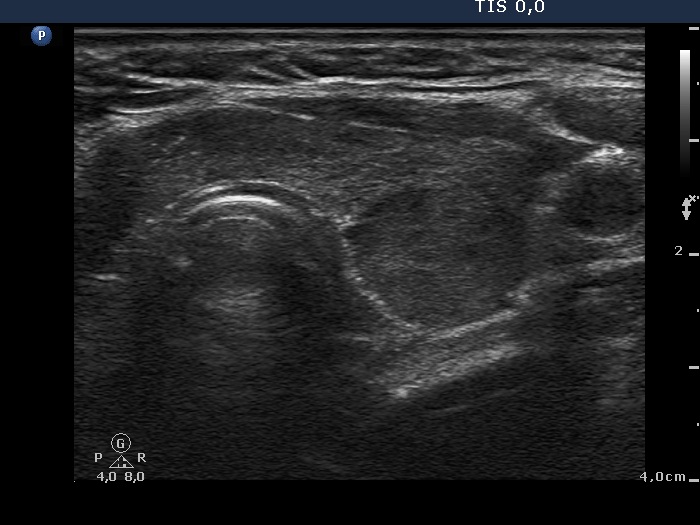

Clinical data: a 52-year-old hypothyroid woman was referred for an evaluation of a nodule detected by an ultrasound examination.

Ultrasonography: the thyroids were moderately hypoechogenic. The dorsal 4/5 of the left lobe was more hypoechogenic. This hypoechogenic area could be followed all along the dorsal part of the left lobe and the isthmus.

Comment: the shape of a nodule is egg- or ball-shaped. A pipe-shaped formation like a vessel or muscle fiber or as in this case a large area of the thyroid with different echo structures may mimic a nodule. But in the latter cases if we put the transducer in line with the formation we can notice the pipe-like shape. Conversely, if we put the transducer in other angles, first of all perpendicular to the object then it seems to be a nodule.